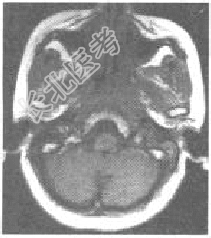

- [材料题] 患者,男性,53岁,发现鼻塞及左侧颈部包块、面部疼痛1个月余,查体左颈部有一质硬包块。MRI如下图所示:

- 简答题1、该患者最可能的诊断为?

- 简答题3、MRI在诊断鼻咽癌中的作用是什么?